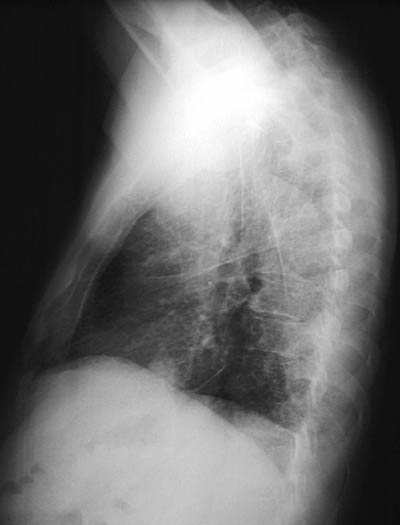

The chest radiograph above in PA view and lateral view below demonstrate a diffuse reticular and nodular pattern of involvement by metastatic carcinoma spreading into the lymphatic channels of the lung.